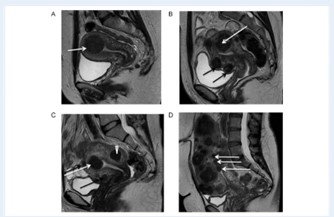

-تصویربرداری رزونانس مغناطیسی (MRI): این نوعی از فناوری تصویربرداری پیشرفته است که تصاویر بسیار دقیقی از اندام های داخلی ارائه می دهد. این تصاویر به ارائه دهنده شما کمک می کند تا محل دقیق و ویژگی های فیبروم را تعیین کند و در صورت نیاز، درمان های کم تهاجمی را برنامه ریزی کند.

-سونوگرافی متمرکز هدایت شده با رزونانس مغناطیسی: همچنین یک تکنیک جدیدتر، امواج صوتی را بر روی فیبروم هایی که در جلوی رحم قرار دارند متمرکز می کند. اثرات بالقوه این روش بر باروری هنوز مشخص نشده است.